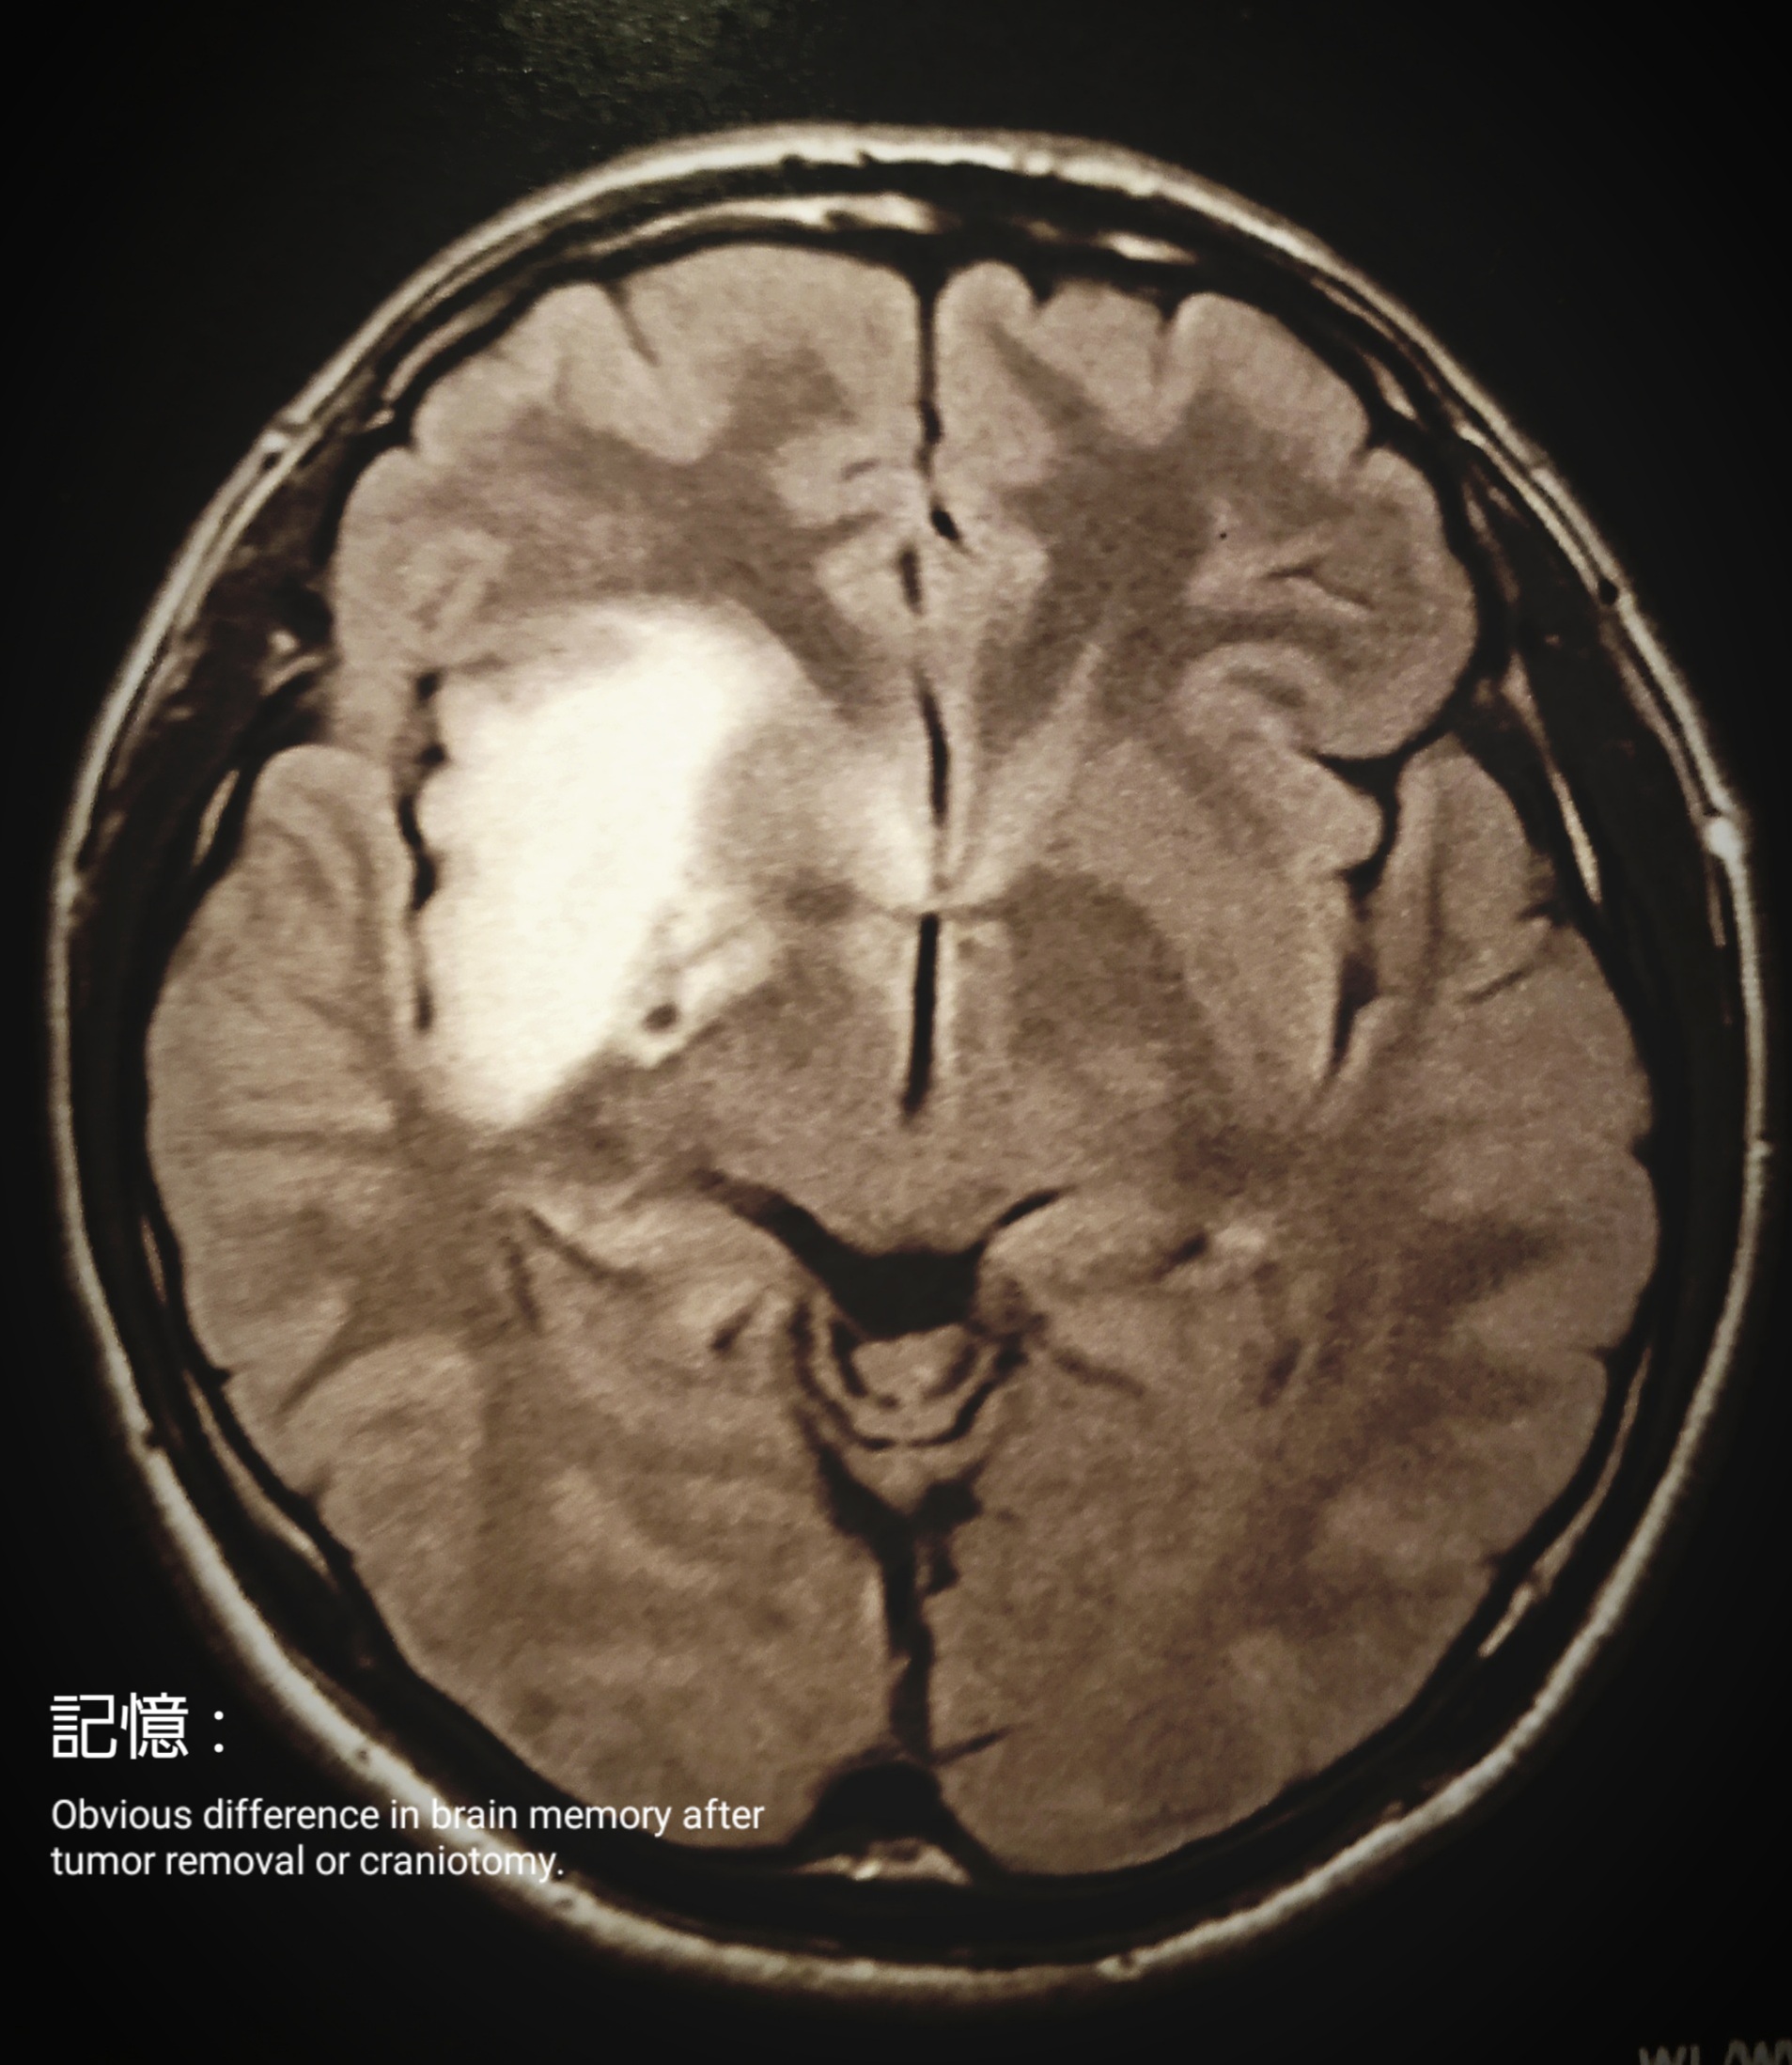

記憶 : 腫瘍摘出、開頭手術後あからさまに感じる脳の記憶力の違い……

記憶 : Obvious difference in brain memory after tumor removal or craniotomy……

Memory : Obvious difference in brain memory after tumor removal or craniotomy……

memory

I’ve never been a good person with a good memory, but

What I’ve felt so clearly lately

No matter how much I try to get the swing into my head or make my body remember it, I can’t remember it at all, as if it goes from right to left.

The pretension that used to be in my head along with my body doesn’t go in at all.

I had heard from my rehabilitation teacher that this kind of thing happens.

A feeling of discomfort in the memory part of my head that I felt during the days leading up to the presentation.